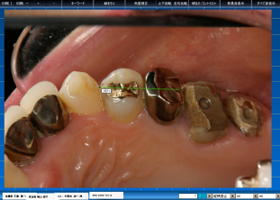

EXAM_VIEW

インターフェイスは2次元CADの感覚。

残存歯列の位置と所見を1歯毎に記録。補綴装置の提案にも利用できます。

口腔内写真や軟組織情報を参考にしながら、口腔内診査情報や所見の入力が可能で、口腔内診査にも使える便利なソフトウェア。

他のファミリーをページ内に表示できるので、デンタルやパノラマ、口腔内写真や、軟組織検査の結果を重ね合わせる事が出来ます。

歯科医師の思考に沿ったインターフェイスだから、無駄なく直感的な入力を支援します。